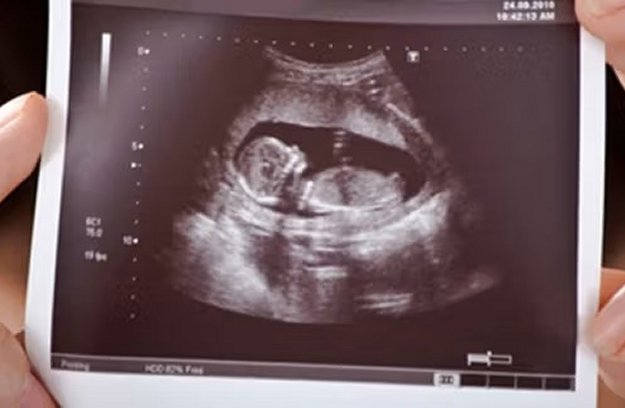

یک متخصص علوم آزمایشگاهی در ایران میگوید که پیش از اجرای قانون «جوانی جمعیت»، نسبت اختلالات کروموزومی که تشخیص داده میشد و به دنیا میآمد، به کل اختلالاتی که به صورت قانونی سقط میشد، نیم درصد بود ولی حالا این نسبت به ۲.۹ درصد رسیده است.

سارنگ یونسی به روزنامه «شرق» گفته است که مراجعه زنان باردار برای انجام غربالگری در آزمایشگاه مدنظر او در تهران، در مقایسه با گذشته بین ۳۰ تا ۴۰ درصد کاهش داشته است.

او همچنین اشاره کرده که پزشکان از درخواست غربالگری در زنان زیر ۳۵ سال بدون داشتن سابقه خانوادگی منع شدهاند مگر خود آنها درخواست تست دهند و اینکه بیمهها نیز همه بیماران را پوشش نمیدهند و هزینههای این کار «به صورت صددرصدی» بر عهده خود افراد است.

بر اساس قانون «جوانی جمعیت و حمایت از خانواده»، ماماها و پزشکان متخصص اجازه پیشنهاد و آموزش ضرورت انجام غربالگری برای تشخیص ناهنجاریهای جنینی را ندارند.

به گزارش صدای آمریکا، از سوی دیگر سارنگ یونسی میگوید محدودیتهای موجود در زمینه واردات کیتهای غربالگری که تا حدی به محدودیتهای ارزی برمیگردد همچنان به قوت خود باقی است.